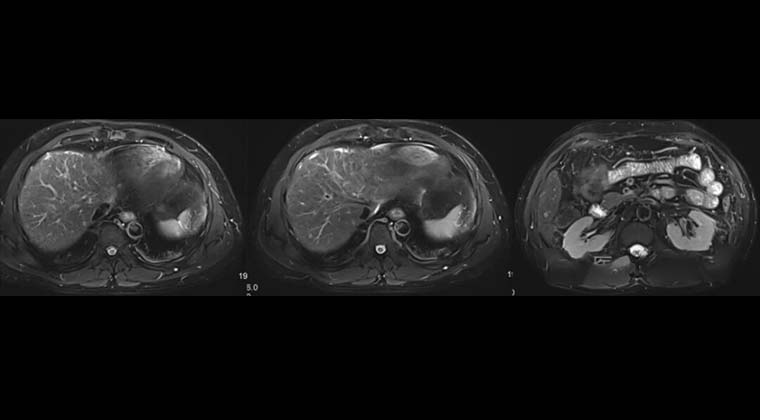

② Случай 2:

Пациент: мужчина, 53 года, злокачественная опухоль печени

(предпроцедурная визуализация)

(визуализация сразу после процедуры)